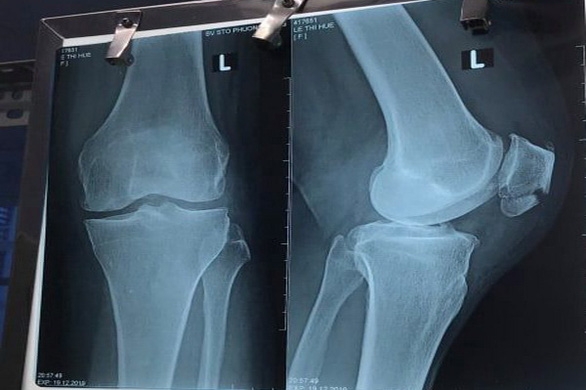

| Phim chụp xương bánh chè của bà H L.T.H. (quê Long An). Ảnh: tuoitre.vn |

Qua quá trình thăm khám, bệnh viện này xác định bệnh nhân tỉnh táo, tiếp xúc tốt, thể trạng trung bình, da, niêm mạc hồng, mạch ổn định và huyết áp cao. Bệnh nhân bị sưng gối trái với chẩn đoán gãy kín xương bánh chè trái. Do đường huyết, huyết áp cao nên bệnh nhân được điều trị nội khoa để hạ.